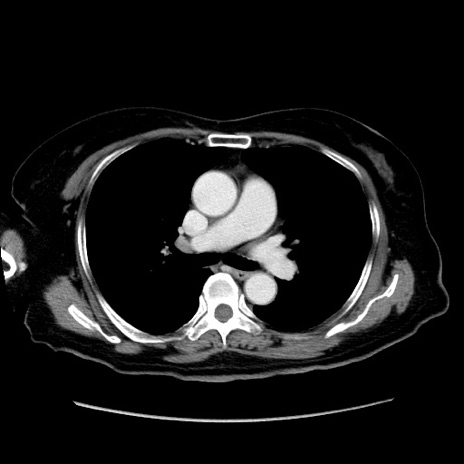

症例19(横断像)

【症例】80歳代女性

【主訴】下腹部痛

【現病歴】約8時間前より下腹部痛の出現あり、救急外来受診。

【既往歴】両側付属器切除

【身体所見】意識清明、下腹部正中に手術痕あり、その部位に一致して圧痛と反跳痛あり。腸蠕動音は亢進。

【データ】WBC 9300、CRP 0.15